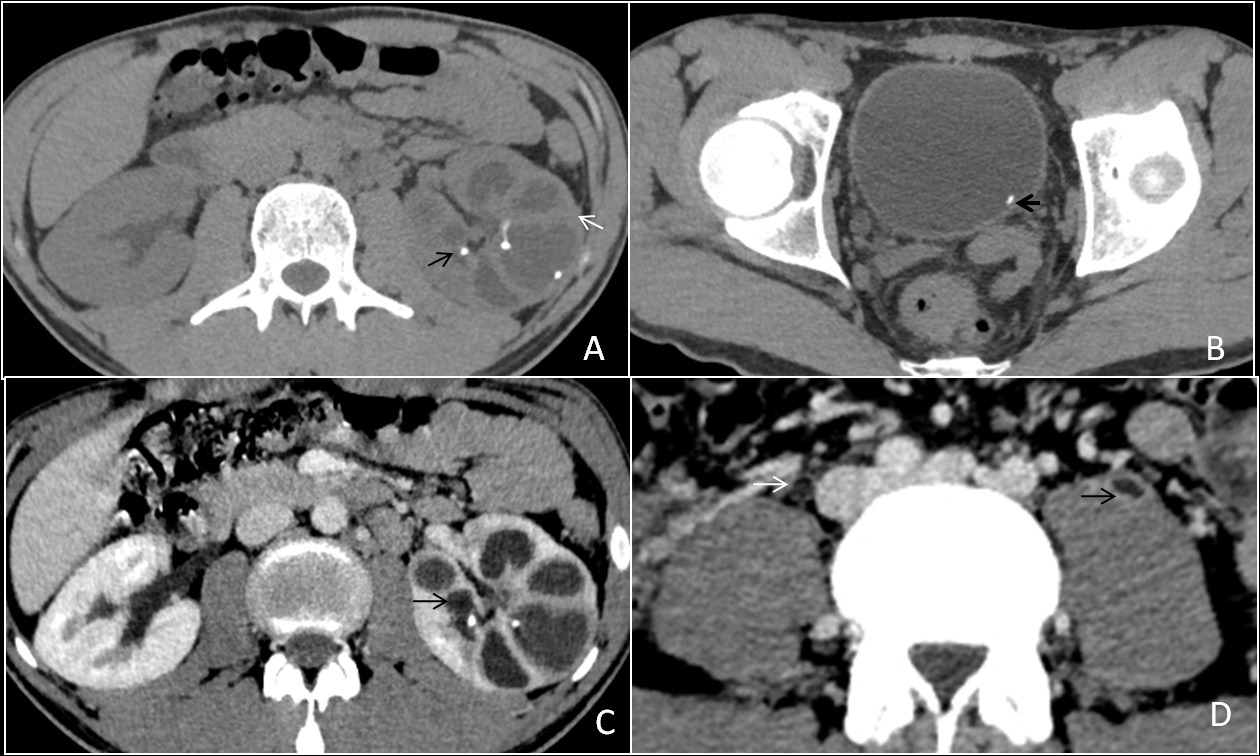

Tubercular peritonitis

Peritoneal involvement is frequently seen in all forms of abdominal tuberculosis. There are three main types of tubercular peritonitis is given [5]. (A) The wet type is in which a large amount of free or loculated viscous fluid is seen. CT findings in this type of peritonitis include high attenuation free fluid (HU value between +25 to +45; signifies high protein and cellular content), (B) the fibrotic fixed type of peritonitis, which is less common and is marked by omental masses, matted mesentery or bowel loops and sometimes loculated ascites, (C) the dry or plastic-type, which is unusual and on CT scan it appears as caseous nodules, fibrous peritoneal reaction, and adhesions. All these described CT features may be confused with peritoneal carcinomatosis [6]. Therefore few features like minimal thickening and enhancement signify TB peritonitis, (Figure 2A,2B) while nodular or irregular thickening implies carcinomatosis. TB peritonitis has a few other findings like macronodular mesenteric deposits (>5 mm), fibrous wall covering the omentum (cocoon abdomen) (Figure 2), and peritoneal or extraperitoneal masses with internal calcifications. Few studies also state that the spreading of inflammation through the peritoneal to the extraperitoneal compartment is specific for TB infection [7].

Figure 2: Two patients, a 35 years old male and a 40 years old female presented with vague pain abdomen, on & off fever and abdominal distension. Contrast-enhanced computed tomography (CECT) abdomen scan demonstrates various forms of involvement in abdominal tuberculosis. (A & B) Axial images from the postcontrast venous phase illustrate peritoneal thickening (white arrow), high density exudative peritoneal fluid (HU=35 to 45) (black arrow), and diffuse mesenteric fat stranding (thick white arrow). Peritoneal fluid cytology demonstrated the presence of lymphocytes, and biochemistry revealed high adenosine deaminase enzyme value (83IU/L), labelling the diagnosis of TB in the endemic regions. The patients underwent a therapeutic ascitic tap and started on antitubercular drugs

Primary intestinal involvement in tuberculosis is uncommon. The gastrointestinal involvement occurs through ingestion of infective organism with sputum or food via hematogenous route or direct spread from the adjacent organ. Tuberculosis is the infection which can involve any segment of the gastrointestinal tract and in colon it forms coccon formation (Figure 3) and the ileocaecal valve, terminal ileum and caecum are found to be more commonly involved; in approximately 90% of intestinal tuberculosis (Figure 4A,4B), it cal also involved colon part as one of our patient has ascending colon thickening and came out to be tubercular (Figure 5). Rectal involvement in tuberculosis is also rare, which represents fistula formation or fibrosis with rectal inflammation. Clinical presentations of rectal tuberculosis are hematochezia and constipation.

Major imaging findings seen in the intestine are symmetrical or asymmetrical bowel wall thickening, fistulae, altered enhancement, or mesenteric fat stranding and strictures are seen in chronic infection. A pulled up caecum is seen into the right subhepatic space due to retraction of the surrounding mesentery. A conglomeration of findings such as asymmetry of the ileocecal valve, the cecal wall thickening, intra-caecal absorption of the terminal ileum, along lymphadenopathy is evocative of tuberculosis [4]. When tuberculosis is suspected, a surgical biopsy should be done to establish the diagnosis.

Figure 4: (A,B) A 25 years old lean and thin female presented with disturbed bowel habits and pain abdomen with on & off fever from last few months. A contrast-enhanced computed tomography scan in the axial plane (A & B) demonstrate thickening of the terminal ileum, ileo-caecal junction and caecum, causing lumen obliteration with surrounding mesenteric fat stranding (white arrow). After colonoscopy guided biopsy, it was proven to be intestinal tuberculosis. The patient had a standard four-drug regimen of ATT for six months, and after that, she was symptoms free.

Figure 5: A 45 years old female presented with pain abdomen and chronic diarrhea. A contrast-enhanced computed tomography axial image from the venous phase demonstrates circumferential thickening of ascending colon (black arrow) with adjacent fat stranding (white arrow). Diagnosis of colonic TB was made through endoscopy guided biopsy. The patient received antitubercular drugs and is recovering well.